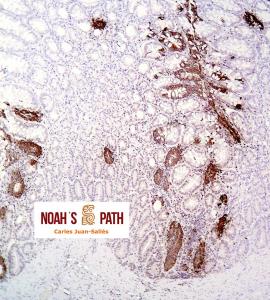

Estudio clínico-patológico e inmunohistoquímico de un brote de mortalidad en elands juveniles debido a infección intestinal por coronavirus en colaboración con Santiago Borragán del Parque de la Naturaleza de Cabárceno y Pepe Ramos de la University of Purdue.